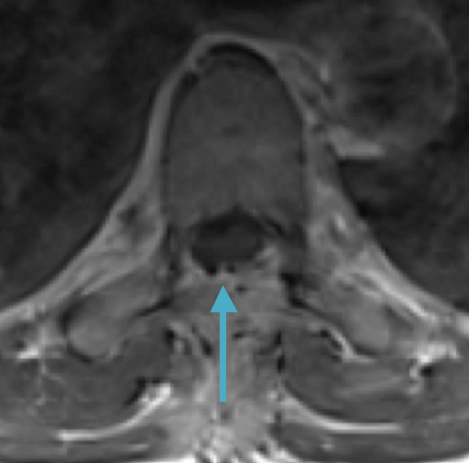

Preoperative MRI T2 demonstrating obstruction of CSF around the cord (blue arrow), resulting from the tumor (red arrow)

Postoperative MRI T2 illustrating the restoration of CSF surrounding the cord (blue arrow)